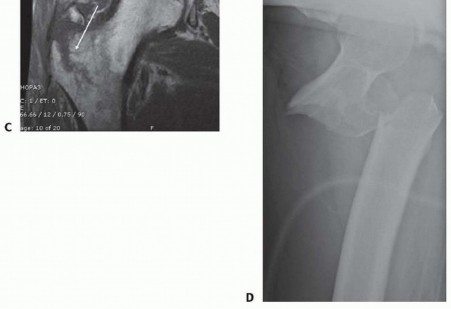

---

### FIG 1 • A. AP radiograph of an AO/OTA type 31-A1 pertrochanteric hip fracture. B. Traction radiograph; note the reduction seen with traction. C. MRI scan of a painful right hip showing an occult peritrochanteric fracture (arrow) not seen on plain radiographs. D. Lateral radiograph of an AO/OTA type 31-A3 intertrochanteric fracture. Note the displacement of this high-energy fracture, occurring in a young patient.